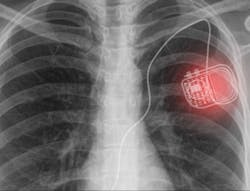

Most implantable medical devices such as pacemakers require a constant source of energy to operate, which has limitations. For example, batteries have a finite lifespan and once the battery power gets exhausted, there is no other option but to perform invasive surgery to replace the battery, which poses a risk of surgical complications such as bruising, infections, and other adverse events.

Recognizing this, a team of researchers at the Gwangju Institute of Science and Technology (GIST; Gwangju, South Korea), led by Professor Jongho Lee, has developed a strategy to recharge the internal battery of medical implant devices without invasive surgery or risky penetrative procedures.